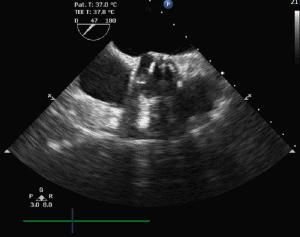

患者女,85岁,术中经食道超声评估,为三叶瓣,重度钙化,瓣环径20mm,左室流出道19mm,法式窦29mm,STJ21.5mm较小,双冠高度可。